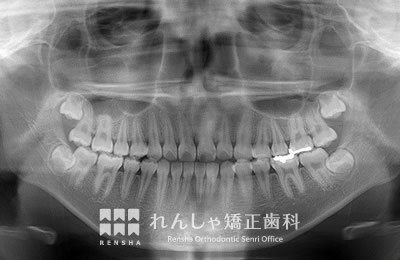

中高生

永久歯列はほぼ完成してしますが、歯列を側方だけでなく後方へも拡大し、埋まっていた右上奥歯を引っ張り出しています。

| 主訴 | 埋まったままでてこない歯がある |

|---|---|

| 診断名 | Angle Class II 小臼歯の埋伏と叢生を伴う上顎前突 |

| 初診時年齢 | 13歳5か月 |

| 装置名 | マルチブラケット装置 |

| 抜歯非抜歯 | 非抜歯 |

| 治療期間 | 2年3か月 |

| 費用の目安 | 約82万円+消費税(検査料金、都度の処置費用等も合わせた総額) |

| リスク副作用 | 歯の移動に伴う軽微な歯根吸収、歯槽骨吸収、歯肉退縮(本症例では軽度の歯根吸収を認めた)、矯正器具装着中のカリエスリスク増大(本症例ではカリエス発生無し) |